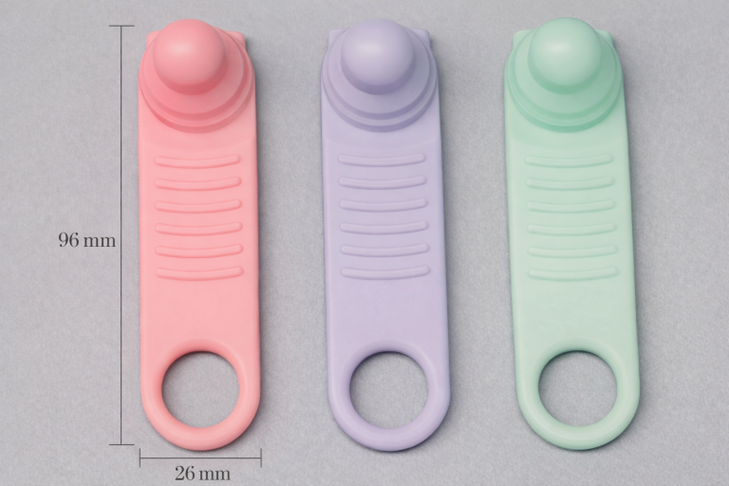

午前-108

口腔機能訓練器具の写真を別に示す。 この器具を用いた機能訓練で改善が期待できる発音はどれか。2つ選べ。

a. ヒ

b. フ

c. マ

d. ヨ

解答を見る

a.d